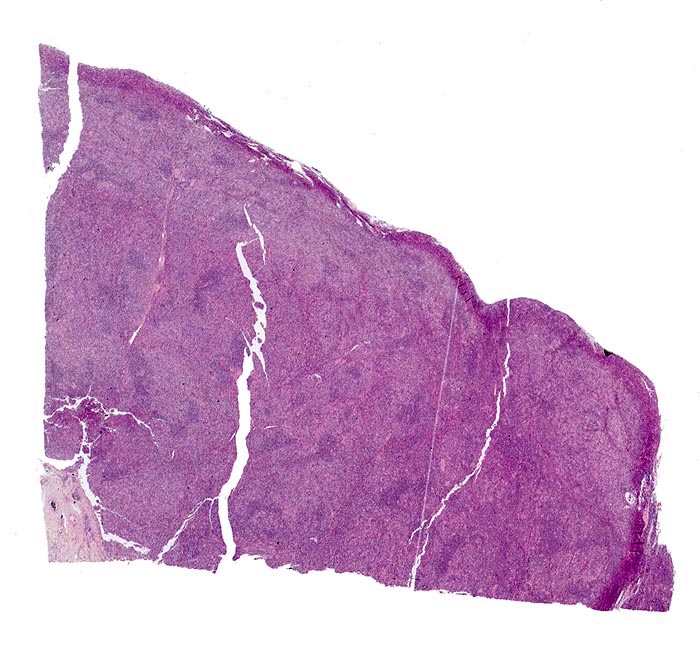

PathoPic ID 3884 - Hodgkin-Lymphom, Mischzelltyp

Hodgkin-Lymphom, Mischzelltyp

Lymphknoten, Kopf-cervikal

Vollständige Aufhebung der normalen Lymphknotenstruktur. Lymphfollikel sind nicht vorhanden.

Vergrösserte zervikale und axilläre Lymphknoten, Fieber und Nachtschweiss.